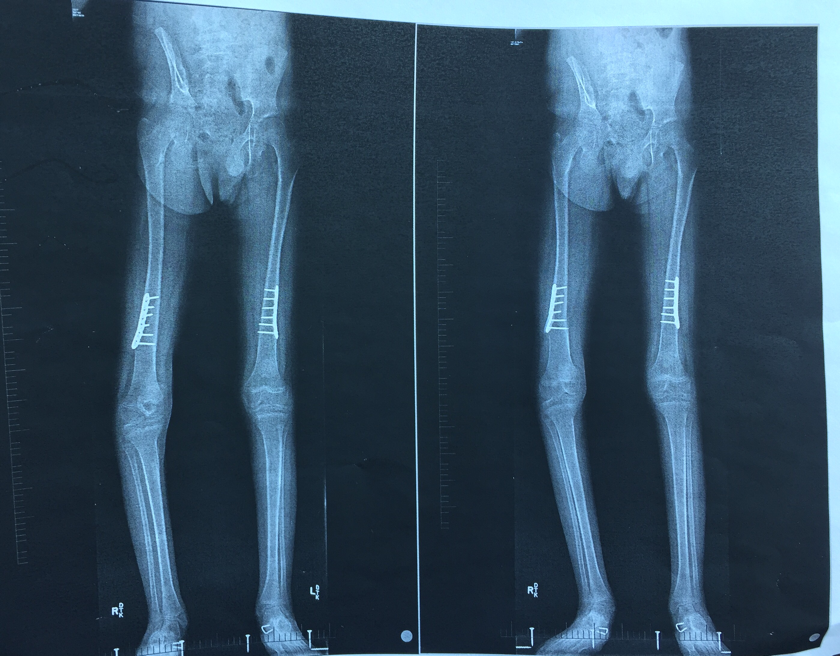

We found out today that Ryan will be having another surgery on August 9th. The surgery he had in spring of 2016 we thought would fix the turning out of his right foot. It did fix the problem on his left foot but his right one still turns out horribly. If you look at the x-ray below, the left picture shows his foot in the right position, the right one shows his kneecap in the correct position. As you can see, you cannot align both at the same time. The good news is that it should be an easy recovery. Outpatient surgery followed by a short leg waterproof cast that he can immediately weight bear on. Plus, it will be a week before school starts so he'll have time to get used to it. On a scale of Ryan surgeries, this should be a pretty easy one. Hopefully!